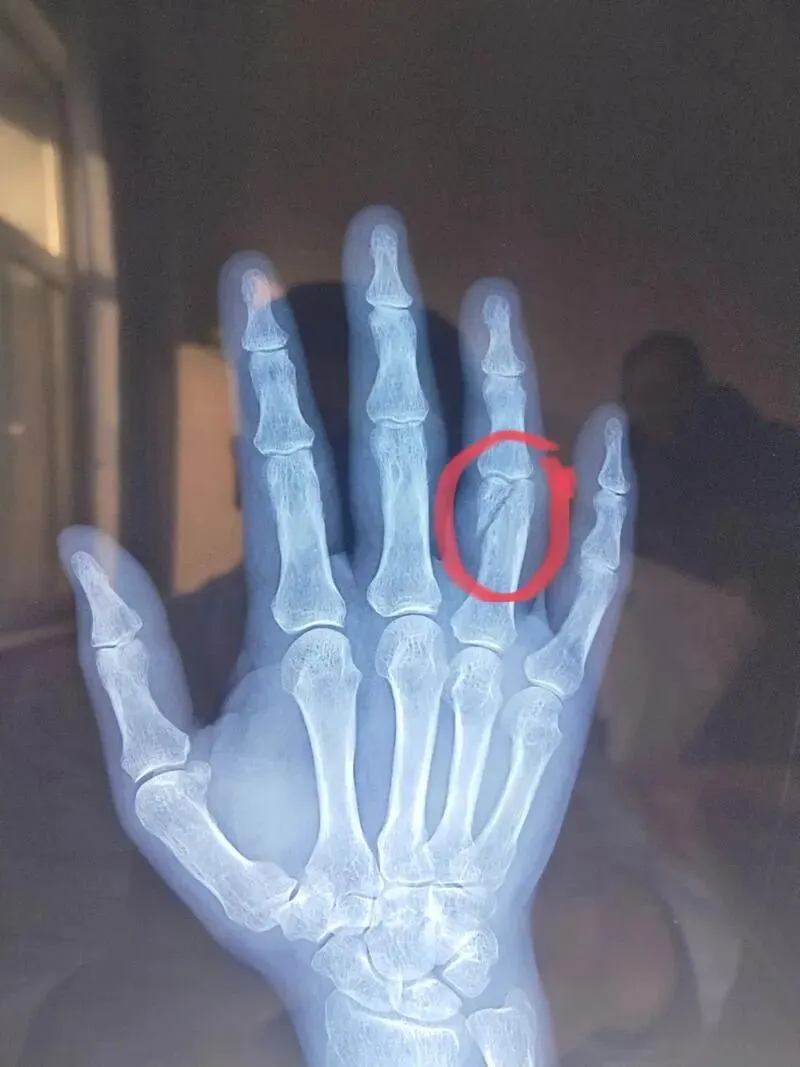

致两人手部受伤,其中一位差点骨折

。(据知情人士透露:有事发日当时

(图片来源于知情人士提供的录像截图)